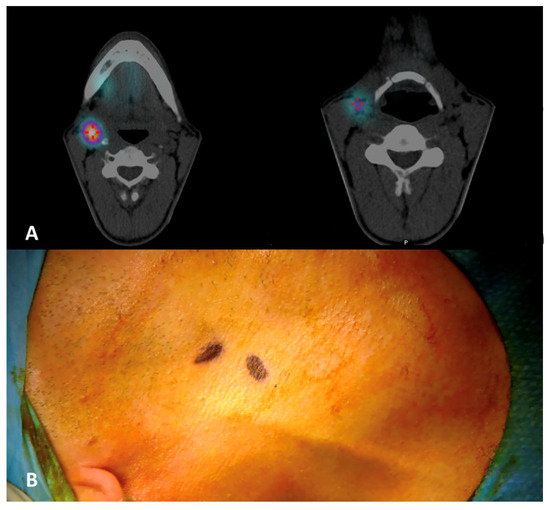

A 71-year-old man with a histologically proven left ventral tongue margin cT1 cN0 squamous cell carcinoma (SCC) was submitted to this protocol after a thorough radiological assessment (head and neck contrast-enhanced magnetic resonance imaging, neck ultrasound) had excluded obvious lymph node metastasis (Video S1). A preoperative lymphoscintigraphy with 99mTc-Tilmanocept (Lymphoseek®, Navidea Biopharmaceuticals, Inc.; Dublin, OH, USA) was performed about 4 h before surgery, with four submucosal injections around the tumor using an insulin syringe with a 27-gauge needle (0.1 mL per injection, 0.4 mL of total dose, 18 MBq) at cardinal points in healthy mucosa (Figure 1). Immediately after radioisotope injection, planar lymphoscintigraphic images were obtained using a GE Millennium gamma camera, with a high-resolution collimator. A support under the shoulders was positioned to reproduce operative conditions. The acquisition window was set at 140 Kev (±10%); the planar image matrix was 256 × 256. The images were obtained in anterior and posterior views. In addition, we performed single-photon emission computed tomography/computed tomography (SPECT/CT) to provide tomographic acquisition and improve anatomical SLN location. Dynamic acquisition allowed differentiation of the first lymph node relays (proper SLN(s)) from secondary ones: in this case, nodal hotspots were identified at levels IB, IIA and III on the left side and at level III on the right side (Figure 2). Skin landmarking was performed at the end of procedure to aid surgical planning.

Figure 2. (A,B) Preoperative SPECT/CT with identification of multiple nodal hotspots (lighter circular areas encircled by a purplish ring, or, for (2), the purplish region) at levels IB (2), IIA (1) and III (4) on the left side and at level III (3) on the right side; hotspot at the primary injection site was also visible (asterisk).